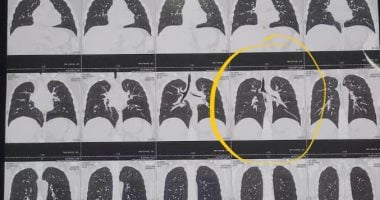

وقال الدكتور عمرو عبد المنعم، إن الطفل كان يلهو بالقلم أثناء قيامه بحل الواجب المدرسي، واضعا غطاء القلم في فمه، شعر بدخول جسم غريب في جوفه مع وجود كحة خفيفة، وبعد أن قام بإخراج القلم اكتشف عدم وجود غطاء في جسم القلم، وتوجهت به أسرته لأحد المستشفيات، وتم إجراء أشعة عادية على الصدر، ولم تظهر وجود أي ج...